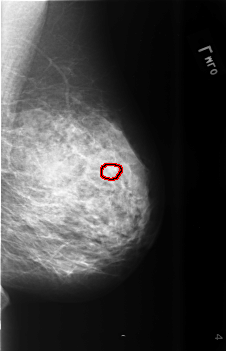

B_3470_1.LEFT_MLO

LEFT_MLO LINES 5616 PIXELS_PER_LINE 3616 BITS_PER_PIXEL 12 RESOLUTION 50 OVERLAY

FILE: B_3470_1.LEFT_MLO.OVERLAY

TOTAL_ABNORMALITIES 1

ABNORMALITY 1

LESION_TYPE CALCIFICATION TYPE PLEOMORPHIC DISTRIBUTION CLUSTERED

ASSESSMENT 4

SUBTLETY 3

PATHOLOGY BENIGN

TOTAL_OUTLINES 1

BOUNDARY